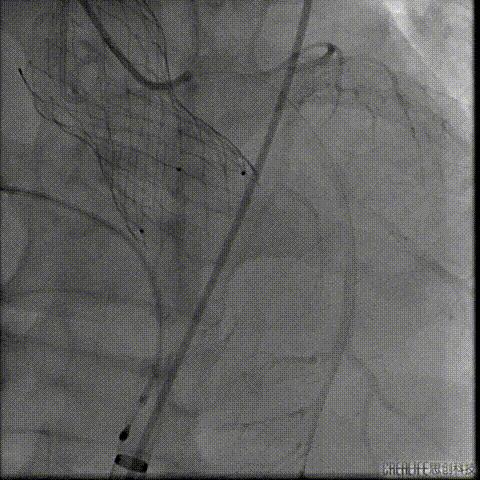

经瓣架网眼挂上指引管

反复确认指引管经瓣架网眼

指引管经瓣架网眼

经网眼置入导丝

置入4.0mm*23mm微创冠脉支架

定位并释放支架